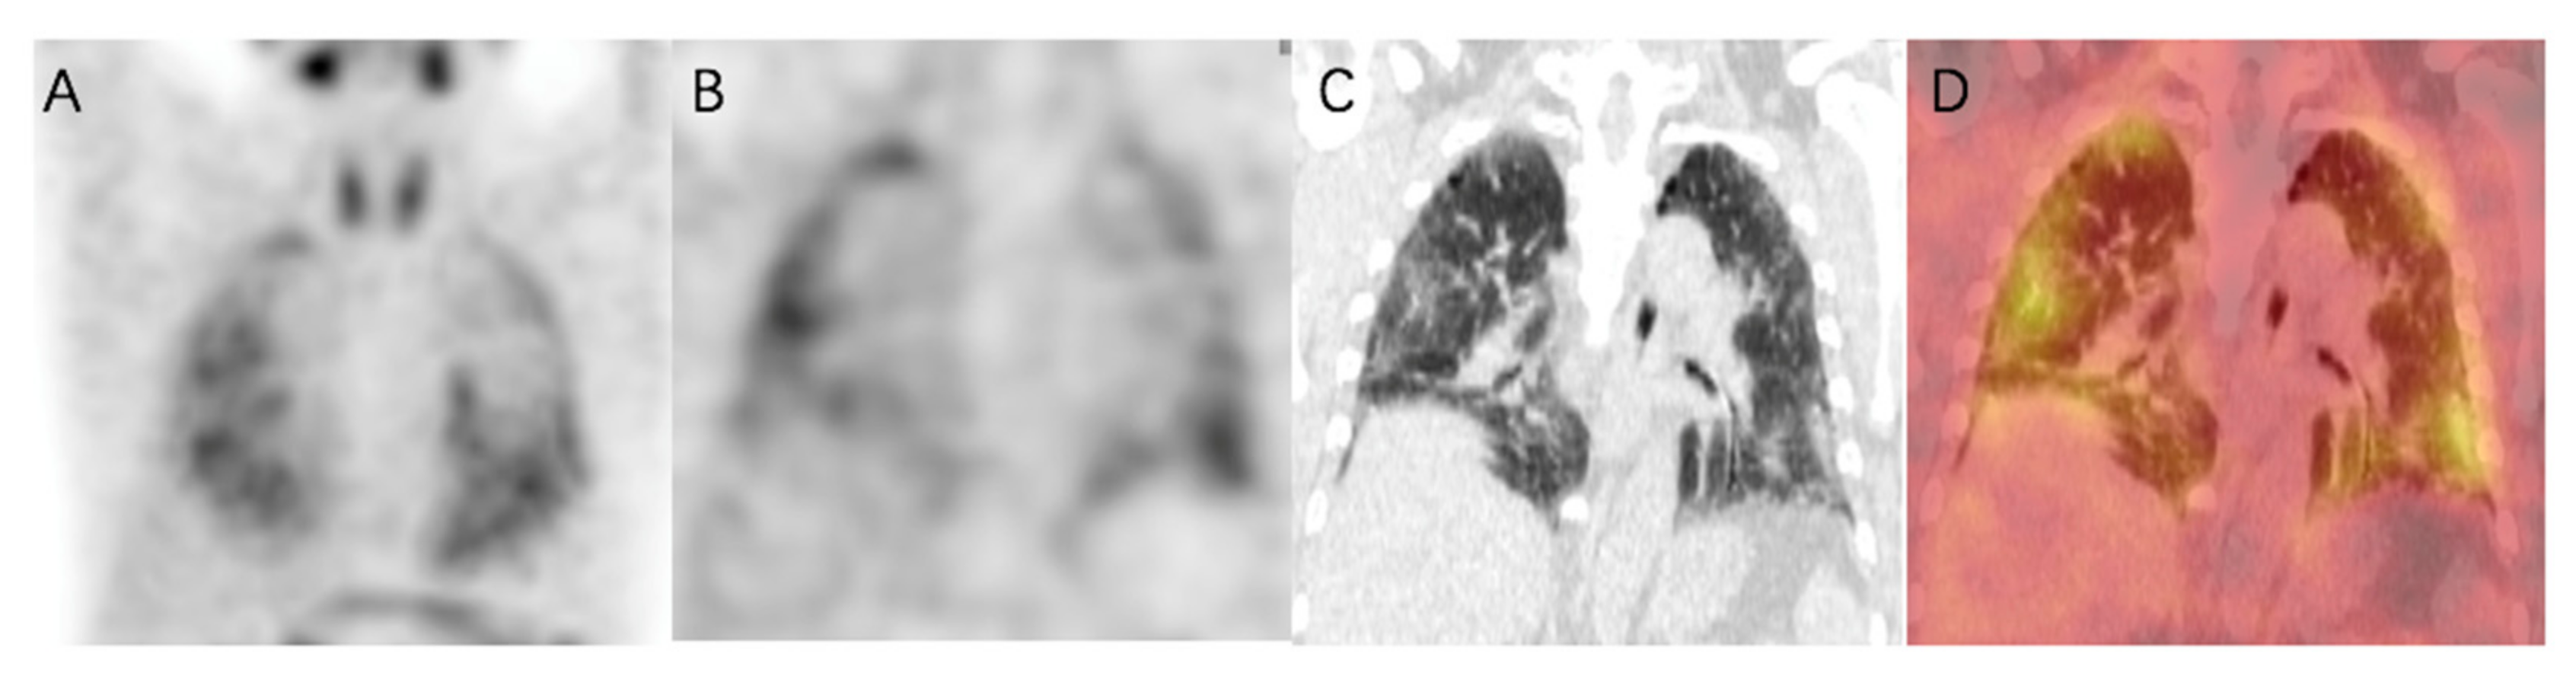

Figure 4. 99mTc-HFAPI SPECT/CT maximum-intensity-projection (MIP) (A), coronal SPECT (B), CT (C), and fused (D) images of a 65-year-old IPF patient. Increased tracer uptake is observed in a subpleural and peripheral distribution, which matches the fibrotic abnormalities in CT images.

2.4. 99mTc-HFAPI Uptake in IPF Patients

In healthy human subjects, there is no pulmonary 99mTc-HFAPI uptake (Figure S2). So, any region of tracer uptake within the lungs was considered abnormal. IPF patients exhibited raised pulmonary 99mTc-HFAPI uptake, with a subpleural and peripheral distribution, involving especially the base of both lungs, as shown in Figure 4. In the corresponding areas of elevated tracer uptake, fibrotic abnormalities, including reticular opacity, traction bronchiectasis, and honeycombing, were observed in HRCT images.